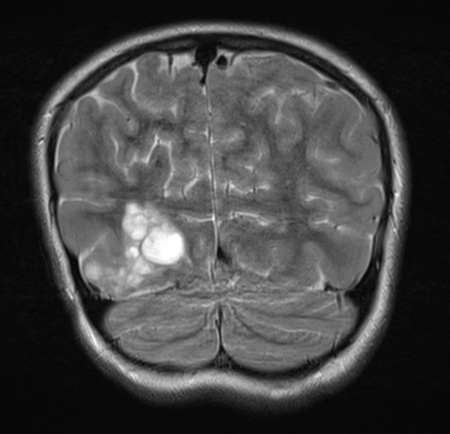

Washington University Experience | NEOPLASMS (NEURONAL) | DNET | 29A4 DNET & Heterotopia (Case 29) T2wC A

The lesion also is multinodular and hyperintense in this T2-weighted scan as seen in coronal (29A4) and sagittal (29A5) sections.